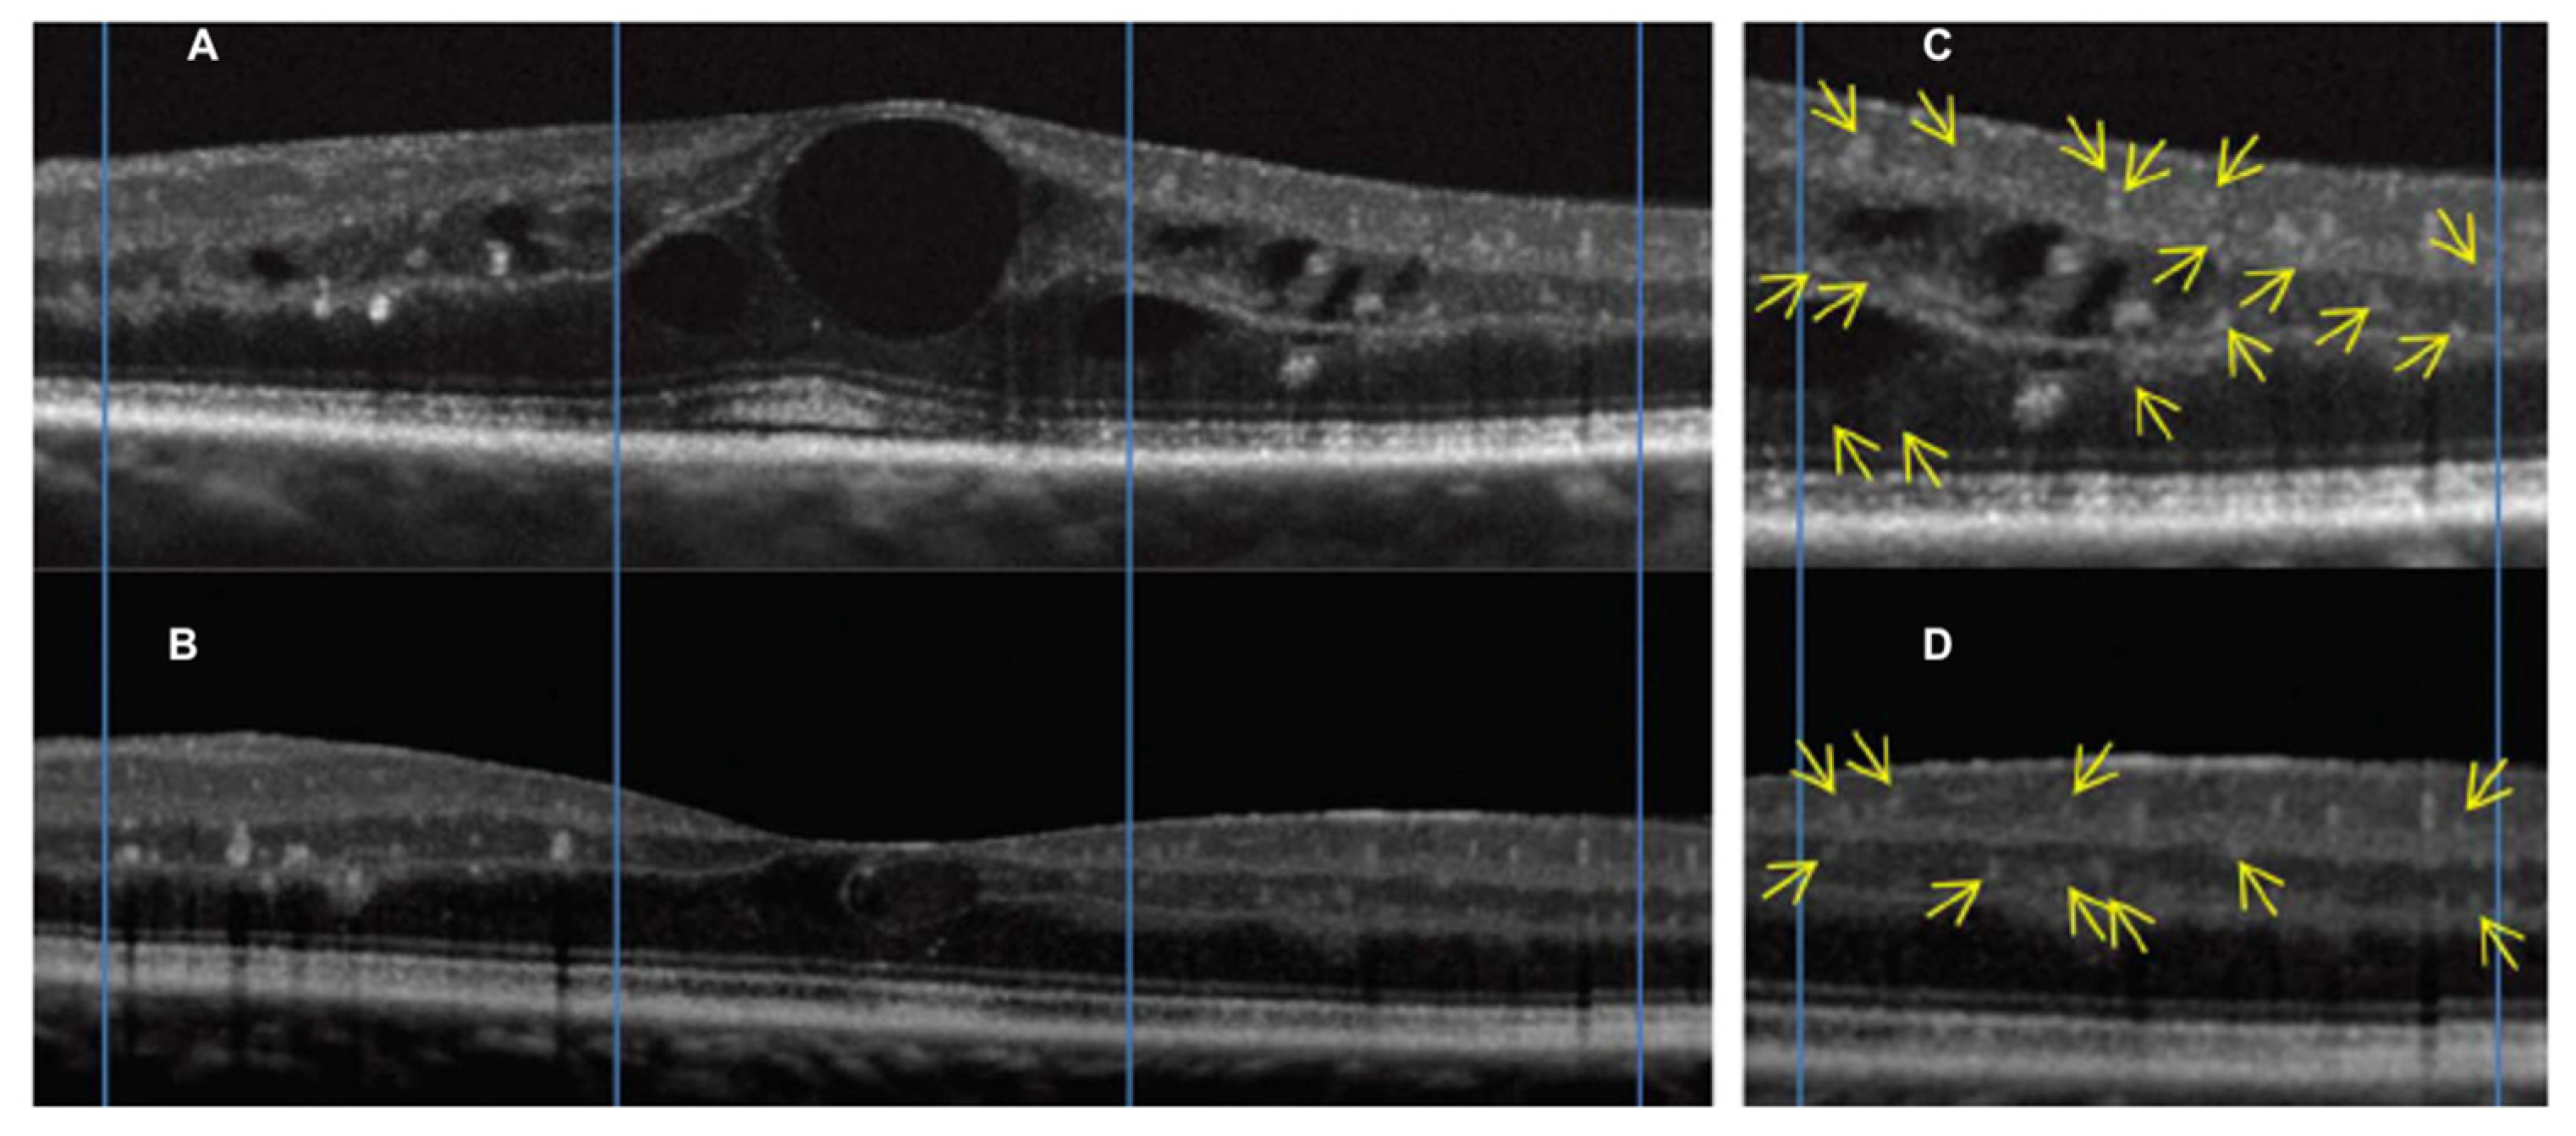

3.1. Radiation (Chorio)Retinopathy

3.2. Radiation Maculopathy

- Frizziero, L.; Parrozzani, R.; Midena, G.; Miglionico, G.; Vujosevic, S.; Pilotto, E.; Midena, E. Hyperreflective intraretinal spots in radiation macular edema on spectral domain optical coherence tomography. Retina 2016, 36, 1664–1669. [Google Scholar] [CrossRef] [PubMed]

- Parrozzani, R.; Midena, E.; Trainiti, S.; Londei, D.; Miglionico, G.; Annunziata, T.; Frisina, R.; Pilotto, E.; Frizziero, L. Identification and classification of macular morphologic biomarkers related to visual acuity in radiation maculopathy. Retina 2020, 40, 1419–1428. [Google Scholar] [CrossRef]